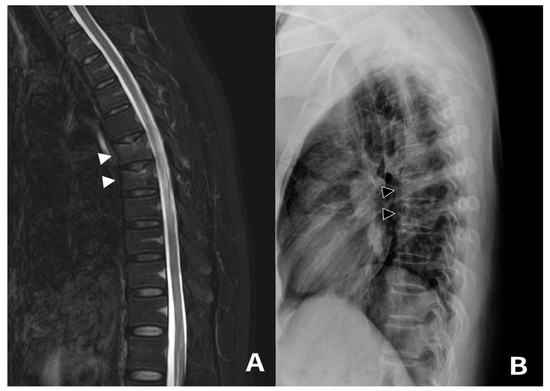

3.1. Case 1 and 2

3.2. Case 3